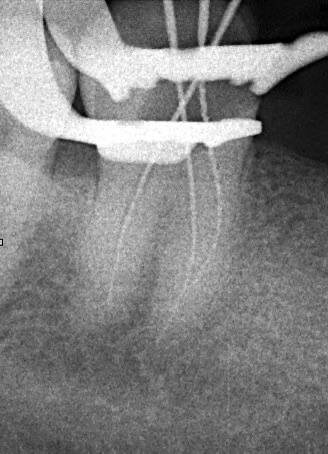

📸 1. Снимок с инструментом в канале

— Это не просто «чтобы было».

— Именно так мы точно определяем рабочую длину, избегая перепломбировки или недопломбировки.

— Без этого как идти по лабиринту вслепую. А пациент заслуживает точности, а не угадывания!